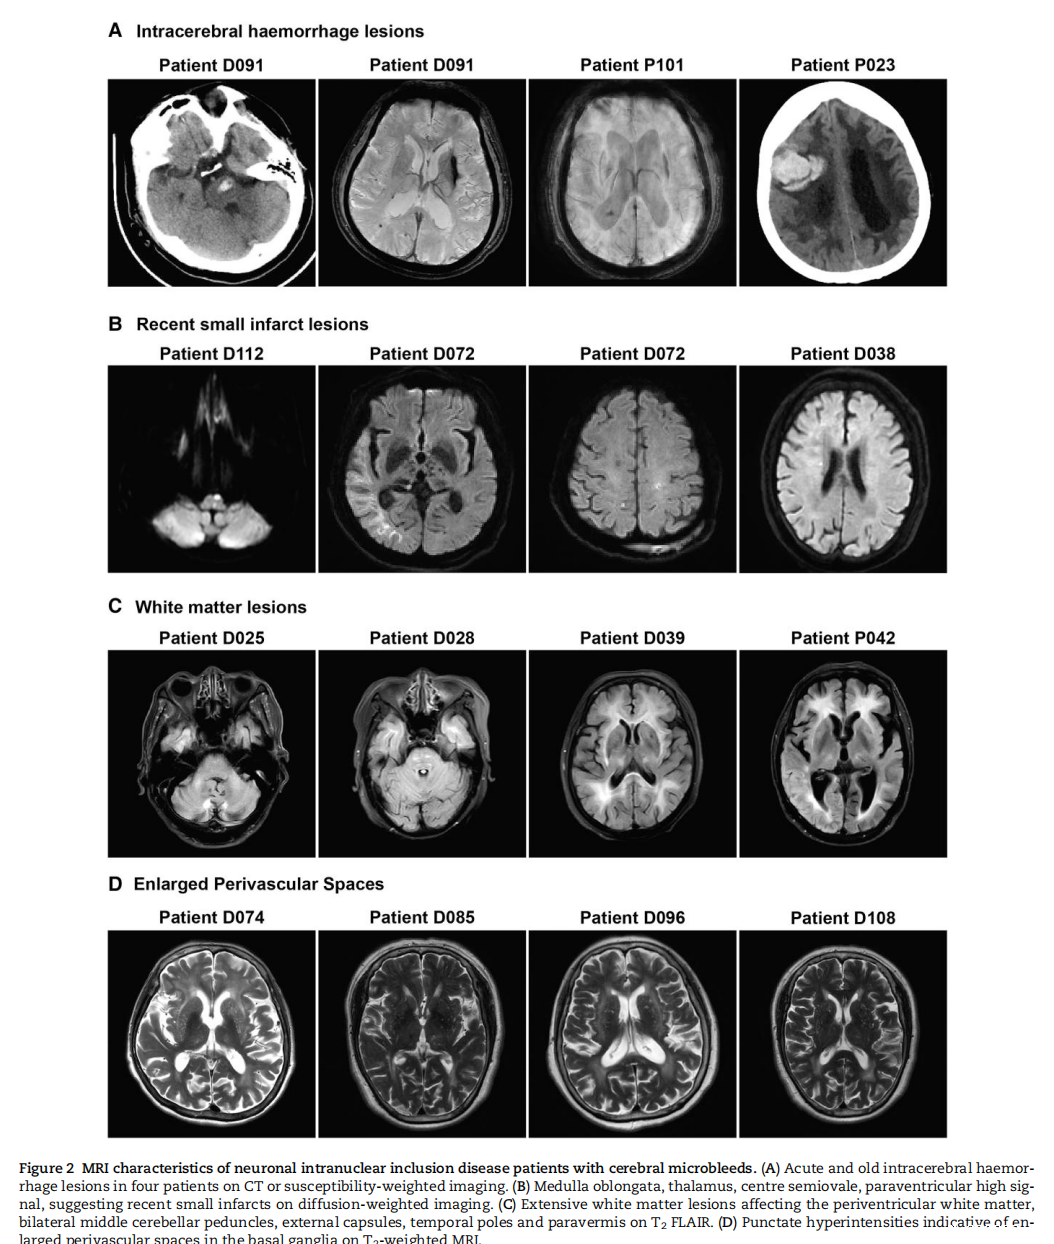

该研究成果显示,NOTCH2NLC 基因 GGC 重复扩增会使其翻译出富含甘氨酸的蛋白质 uN2CpolyG。这种蛋白质不仅会在神经元内聚集形成包涵体,还能沉积在血管壁形成淀粉样物质,导致患者出现进行性认知功能障碍、多发脑微出血、反复皮层下梗死、关键脑区白质病变(外囊、颞极)、脑叶出血等症状。这一发现有助于解释神经元核内包涵体病患者特有的一些临床表现,像卒中样发作、癫痫发作、偏头痛发作、脑炎样发作等,这些症状实际上可能是由脑血管淀粉样变引起的短暂性局灶性神经系统发作(TFNE),即 “淀粉样发作(amyloid spells)”。